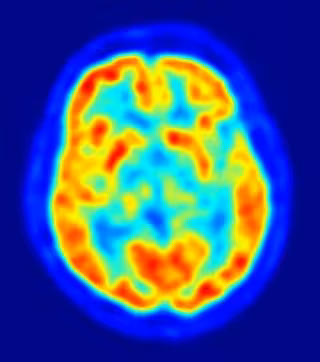

Rauschecker y DeWitt analizaron la literatura científica de estudios que investigan la percepción auditiva del habla en los seres humanos con diferentes métodos de exploración - ya sea a partir de la resonancia magnética funcional (fMRI) o a partir de tomografía por emisión de positrones (PET).

Los científicos encontraron 115 estudios de imágenes cerebrales de la percepción del habla, que en total incluyen a más de 1.900 participantes, y más de 800 coordenadas cerebrales para el procesamiento del habla. A continuación, utilizaron un tipo de análisis que les permitió medir el grado de acuerdo entre las coordenadas del cerebro de estos estudios.

Los resultados señalan la ubicación de la zona de Wernicke que en el lóbulo temporal izquierdo, en concreto, en la circunvolución temporal superior, frente a la corteza auditiva primaria.